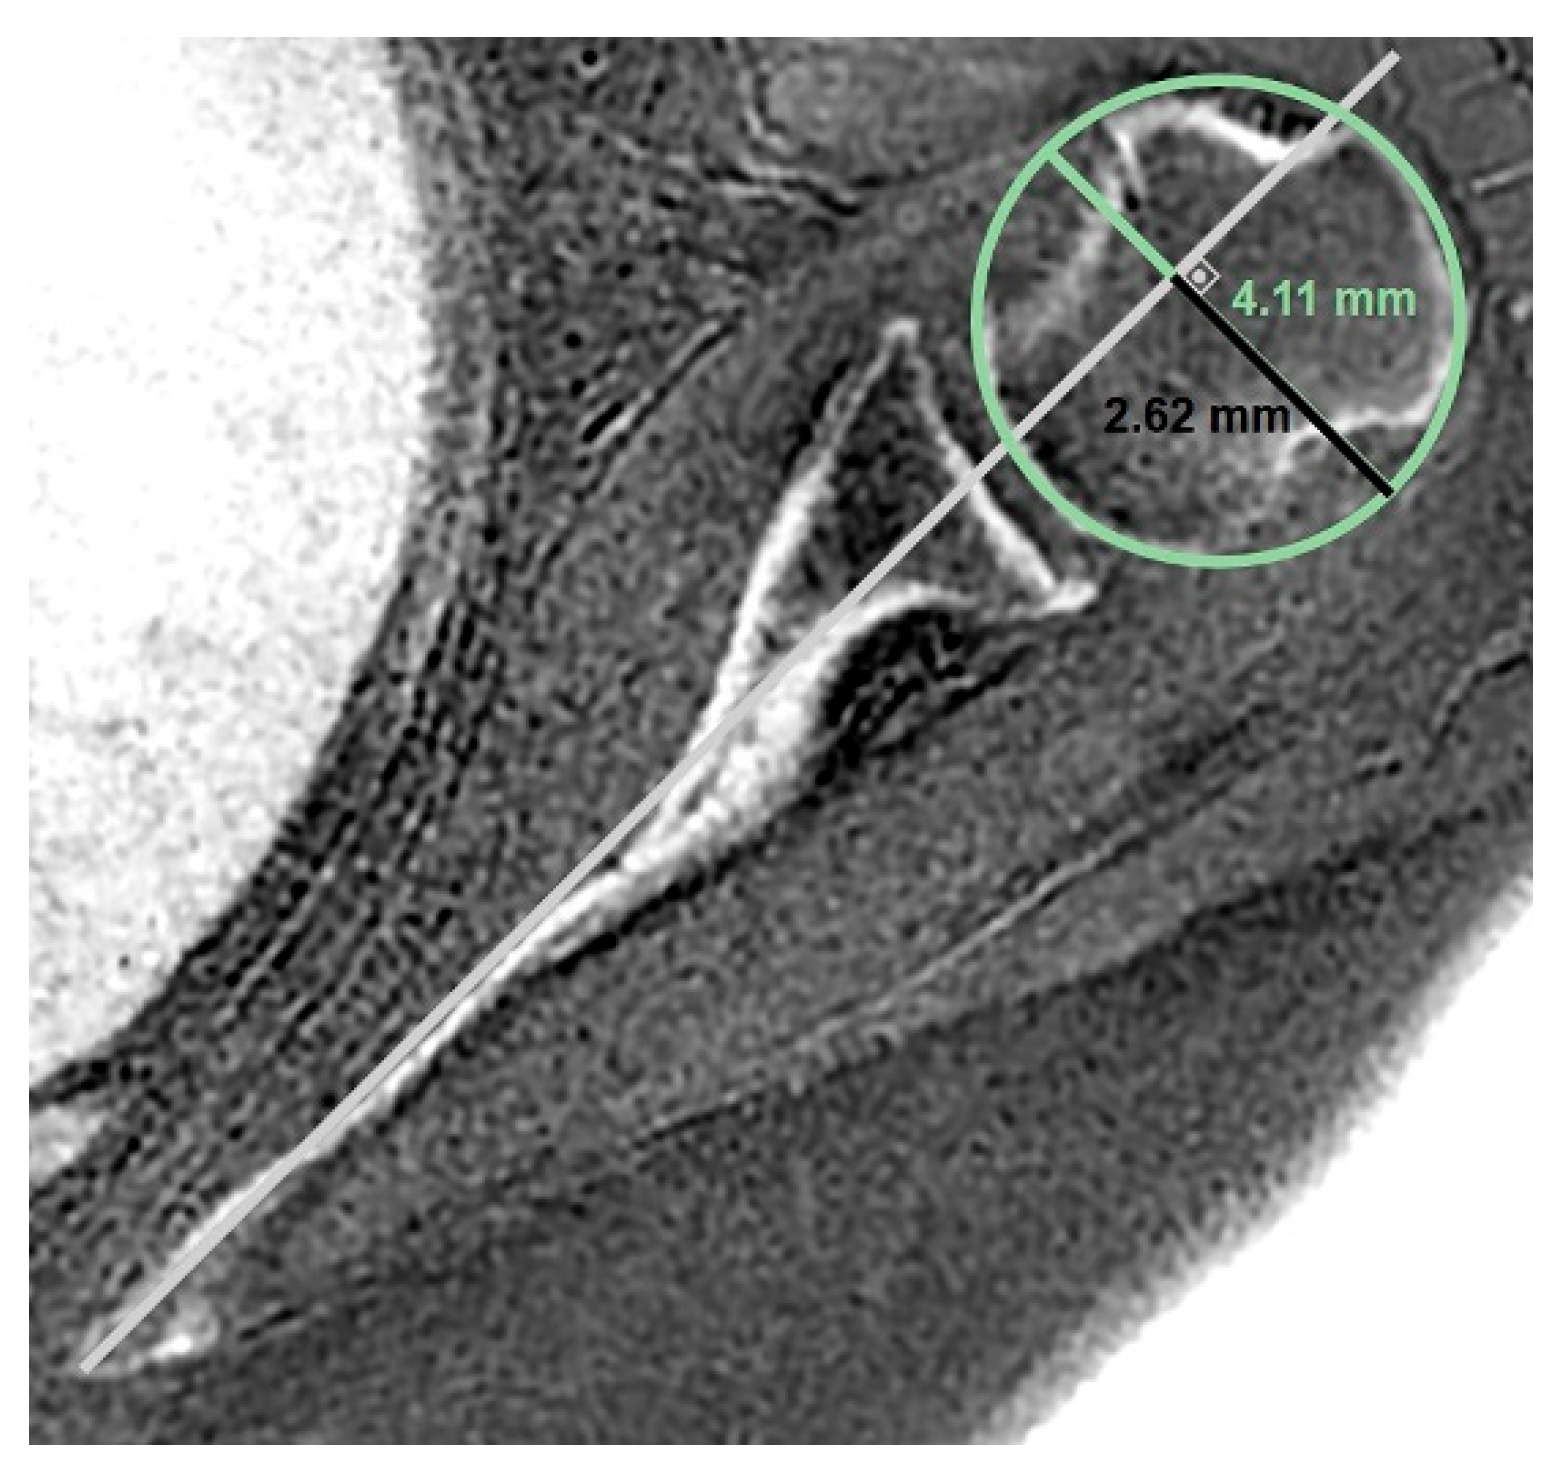

- MRI-based measurements

| Anterior bone loss | 0.917 | 0.776–0.969 | >0.05 | 0.670 | 0.235–0.876 | >0.05 |

| Central bone loss | 0.949 | 0.862–0.981 | >0.05 | 0.788 | 0.525–0.919 | >0.05 |

| Posterior bone loss | 0.925 | 0.748–0.974 | >0.05 | 0.802 | 0.551–0.924 | >0.05 |

| Best-fit circle width | 0.863 | 0.746–0.926 | >0.05 | 0.828 | 0.619–0.916 | >0.05 |

| Glenoid best-fit circle bone loss ratio | 0.818 | 0.546–0.927 | >0.05 | 0.640 | 0.292–0.836 | >0.05 |